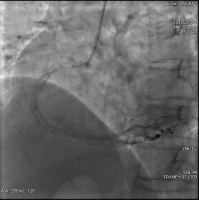

造影结果(二): RCA:近段狭窄85%~90%。

![]()

造影结论及应对策略: LAD:中远段狭窄30%~40%,较长病变。LCX:中段狭窄80%~85%。 RCA:近段狭窄约85%~90%。造影后向患者家属交代病情,与家属沟通后决定择期行介入治疗。